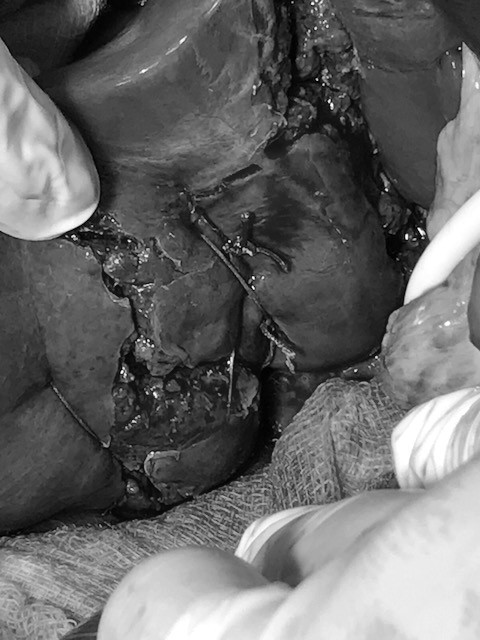

Ekip BS tiến hành phẫu thuật mở bụng cắt lọc khâu gan vỡ cầm máu, cắt lọc mô tụy bị dập, lấy máu tụ sau phúc mạc, rửa và dẫn lưu ổ bụng, dẫn lưu màng phổi bên trái, nẹp bột cố định xương đùi bên phải.